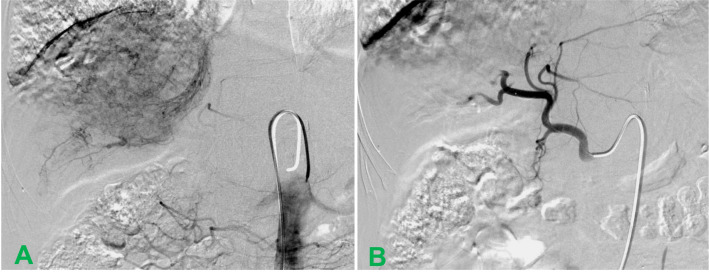

在TACE过程中,采用Seldinger法穿刺右股动脉,置入5F-RH导管至肝右动脉,行常规腹腔动脉及肝总动脉造影。结果显示肝右动脉增粗、血管增多,动脉期肿瘤染色丰富,并可见中晚期肝静脉瘤栓的条带状染色(图3A)。将导管超选至肝右动脉分支,将rAd-p53(5×1012 VP)溶于30 ml生理盐水后,与200 mg粒径350–560 μm的明胶海绵微粒(GSMs)混合。在透视引导下,将上述混合物缓慢栓塞至肿瘤靶动脉。造影剂停滞流动后,暂停2分钟再次造影,确认肿瘤染色完全消失后停止栓塞(图3B)。术中,患者出现轻微胃部疼痛,经静脉注射10 mg地佐辛后完全缓解。术后6小时出现发热,持续10天,最高体温39.1℃,经对症处理后体温渐降至正常。予保肝、支持治疗,术后10天出院。TACE术后第3天开始口服索拉非尼(200 mg/片),初始剂量为400 mg、每日两次。

图3. TACE术中肝动脉造影图像。(A)介入治疗期间,动脉造影显示肿瘤和HVTT明显染色;(B)介入治疗后,肝右动脉分支截断,肿瘤染色完全消失。